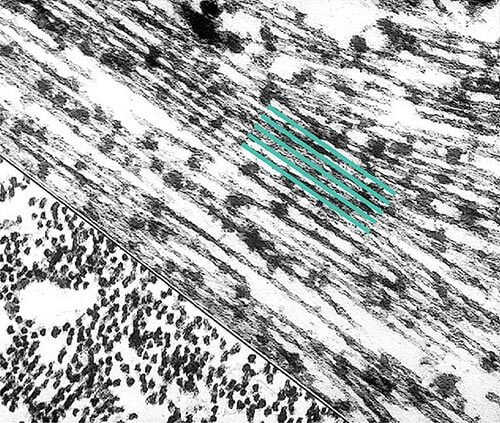

More About Tangles

Tangles destroy a vital cell transport system made of proteins. This electron microscope picture shows a cell with some healthy areas and other areas where tangles are forming.

In healthy areas:

In areas where tangles are forming:

Nutrients and other essential supplies can no longer move through the cells, which eventually die.